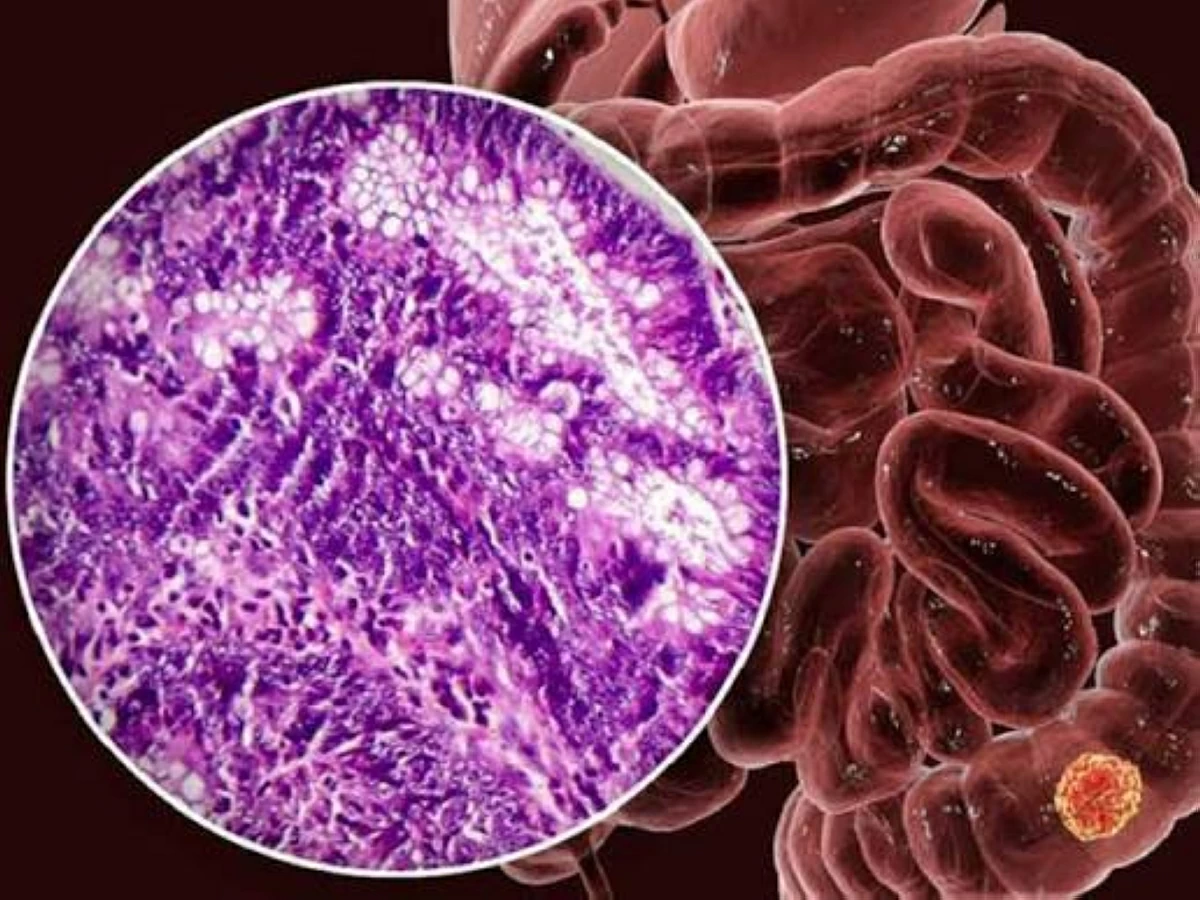

نفت وزارة الصحة والسكان المصرية الشائعات المتداولة بشأن تسبب وسائل منع الحمل الهرمونية في الإصابة بالسرطان أو «المياه على المخ»، مؤكدة أن هذه المزاعم لا تستند إلى أي أدلة علمية، وأن جميع وسائل تنظيم الأسرة المعتمدة آمنة وتخضع لرقابة وتقييمات صارمة قبل إتاحتها للاستخدام....